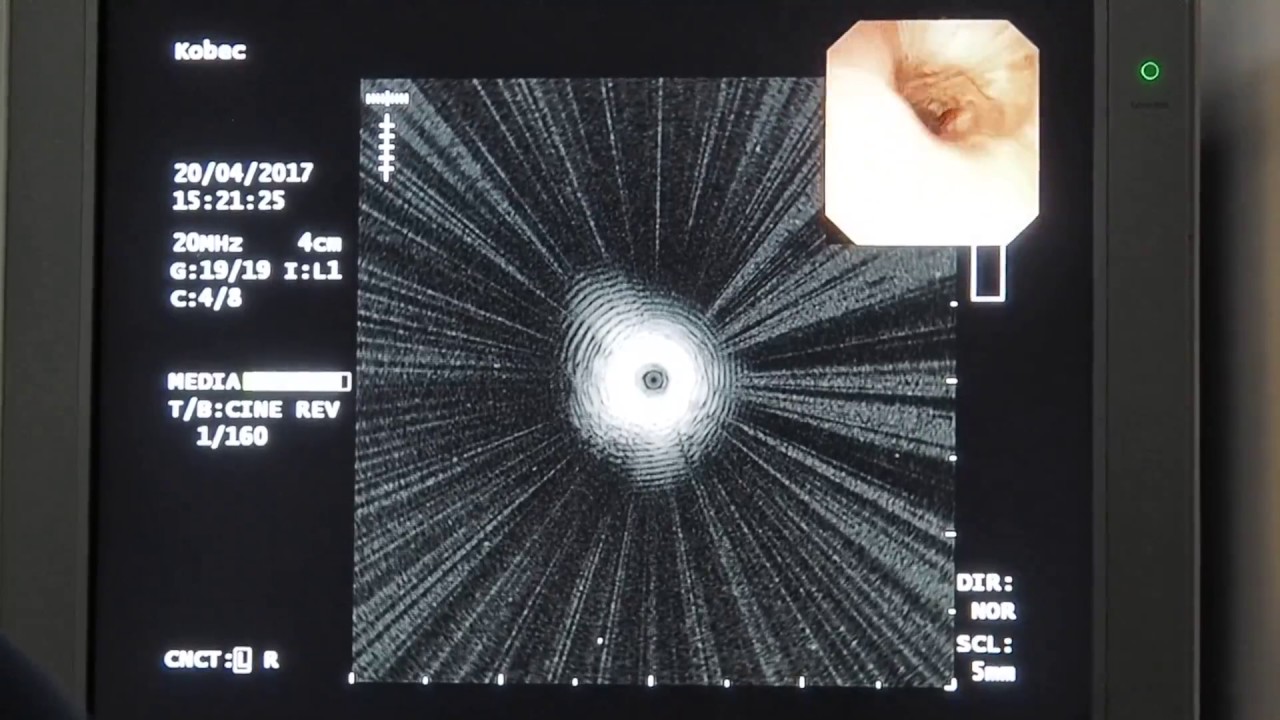

трансбронхиальная биопсия

Бронхоскоп вводится через нос (реже – через рот). Слизистая предварительно орошается раствором лидокаина. Положение пациента обычно – лежа на спине.

Врач последовательно осматривает все отделы бронхиального дерева. Взятие биопсии осуществляется специальными щипцами, вводимыми через инструментальный канал бронхоскопа. Щипцы «выкусывают» кусочек ткани из патологического очага (при узловых образованиях) или из разных мест (при диффузных заболеваниях).

С помощью бронхоскопии иногда производят и трансбронхиальную пункцию лимфоузлов средостения.

Вся процедура занимает 30-50 минут.